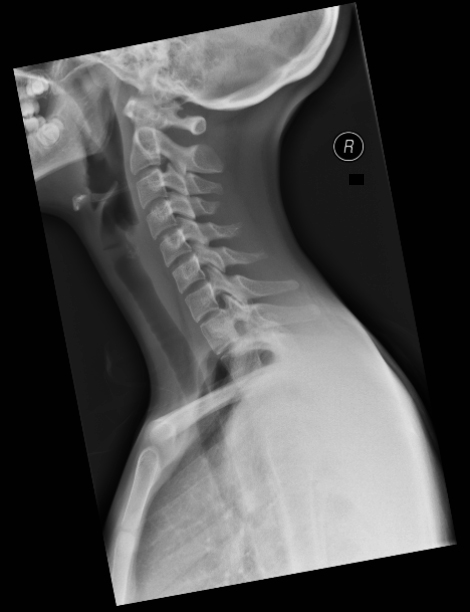

| 2 |

Abnormal fr rt ramus |

Normal |

Incorrect |